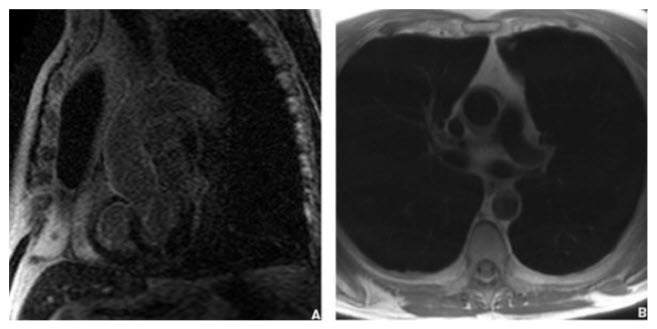

Giant cell arteritis. The presence of systemic symptoms including headaches and myalgias with an elevated sedimentation rate in an elderly woman is suggestive of temporal arteritis. Temporal arteritis affects women twice as often as it does men and is most commonly seen after age 55 years. Temporal artery tenderness may be present with the potential for blindness to occur. Biopsy of the temporal arteries is diagnostic. Associated giant cell arteritis with involvement of the aorta and branch vessels with aneurysm formation may occur. Diagnostic criteria are sensitive and specific for giant cell arteritis if at least three of the following findings are present: (a) >50 years of age, (b) recent onset of localized headaches, (c) temporal artery tenderness or pulse attenuation, (d) erythrocyte sedimentation rate >50 mm/h, and (e) arterial biopsy showing necrotizing vasculitis. The MRA of this patient shows features of vessel thickening of the ascending aorta and arch with “edema”-weighted characteristics and mural enhancement suggestive of an inflammatory aortitis and consistent with giant cell aortitis. Corticosteroids therapy can be used to reduce inflammation seen with aortitis with guidance from serial MRA imaging. Cardiac MRI. Sagittal delayed enhancement (phase-sensitive inversion recovery) image (A) and axial black-blood (double IR) (B) images demonstrating diffuse mural enhancement (A) and thickening of the ascending aorta and arch (B) consistent with an inflammatory arteritis. This patient has giant cell arteritis of the aorta (see figure in the question).